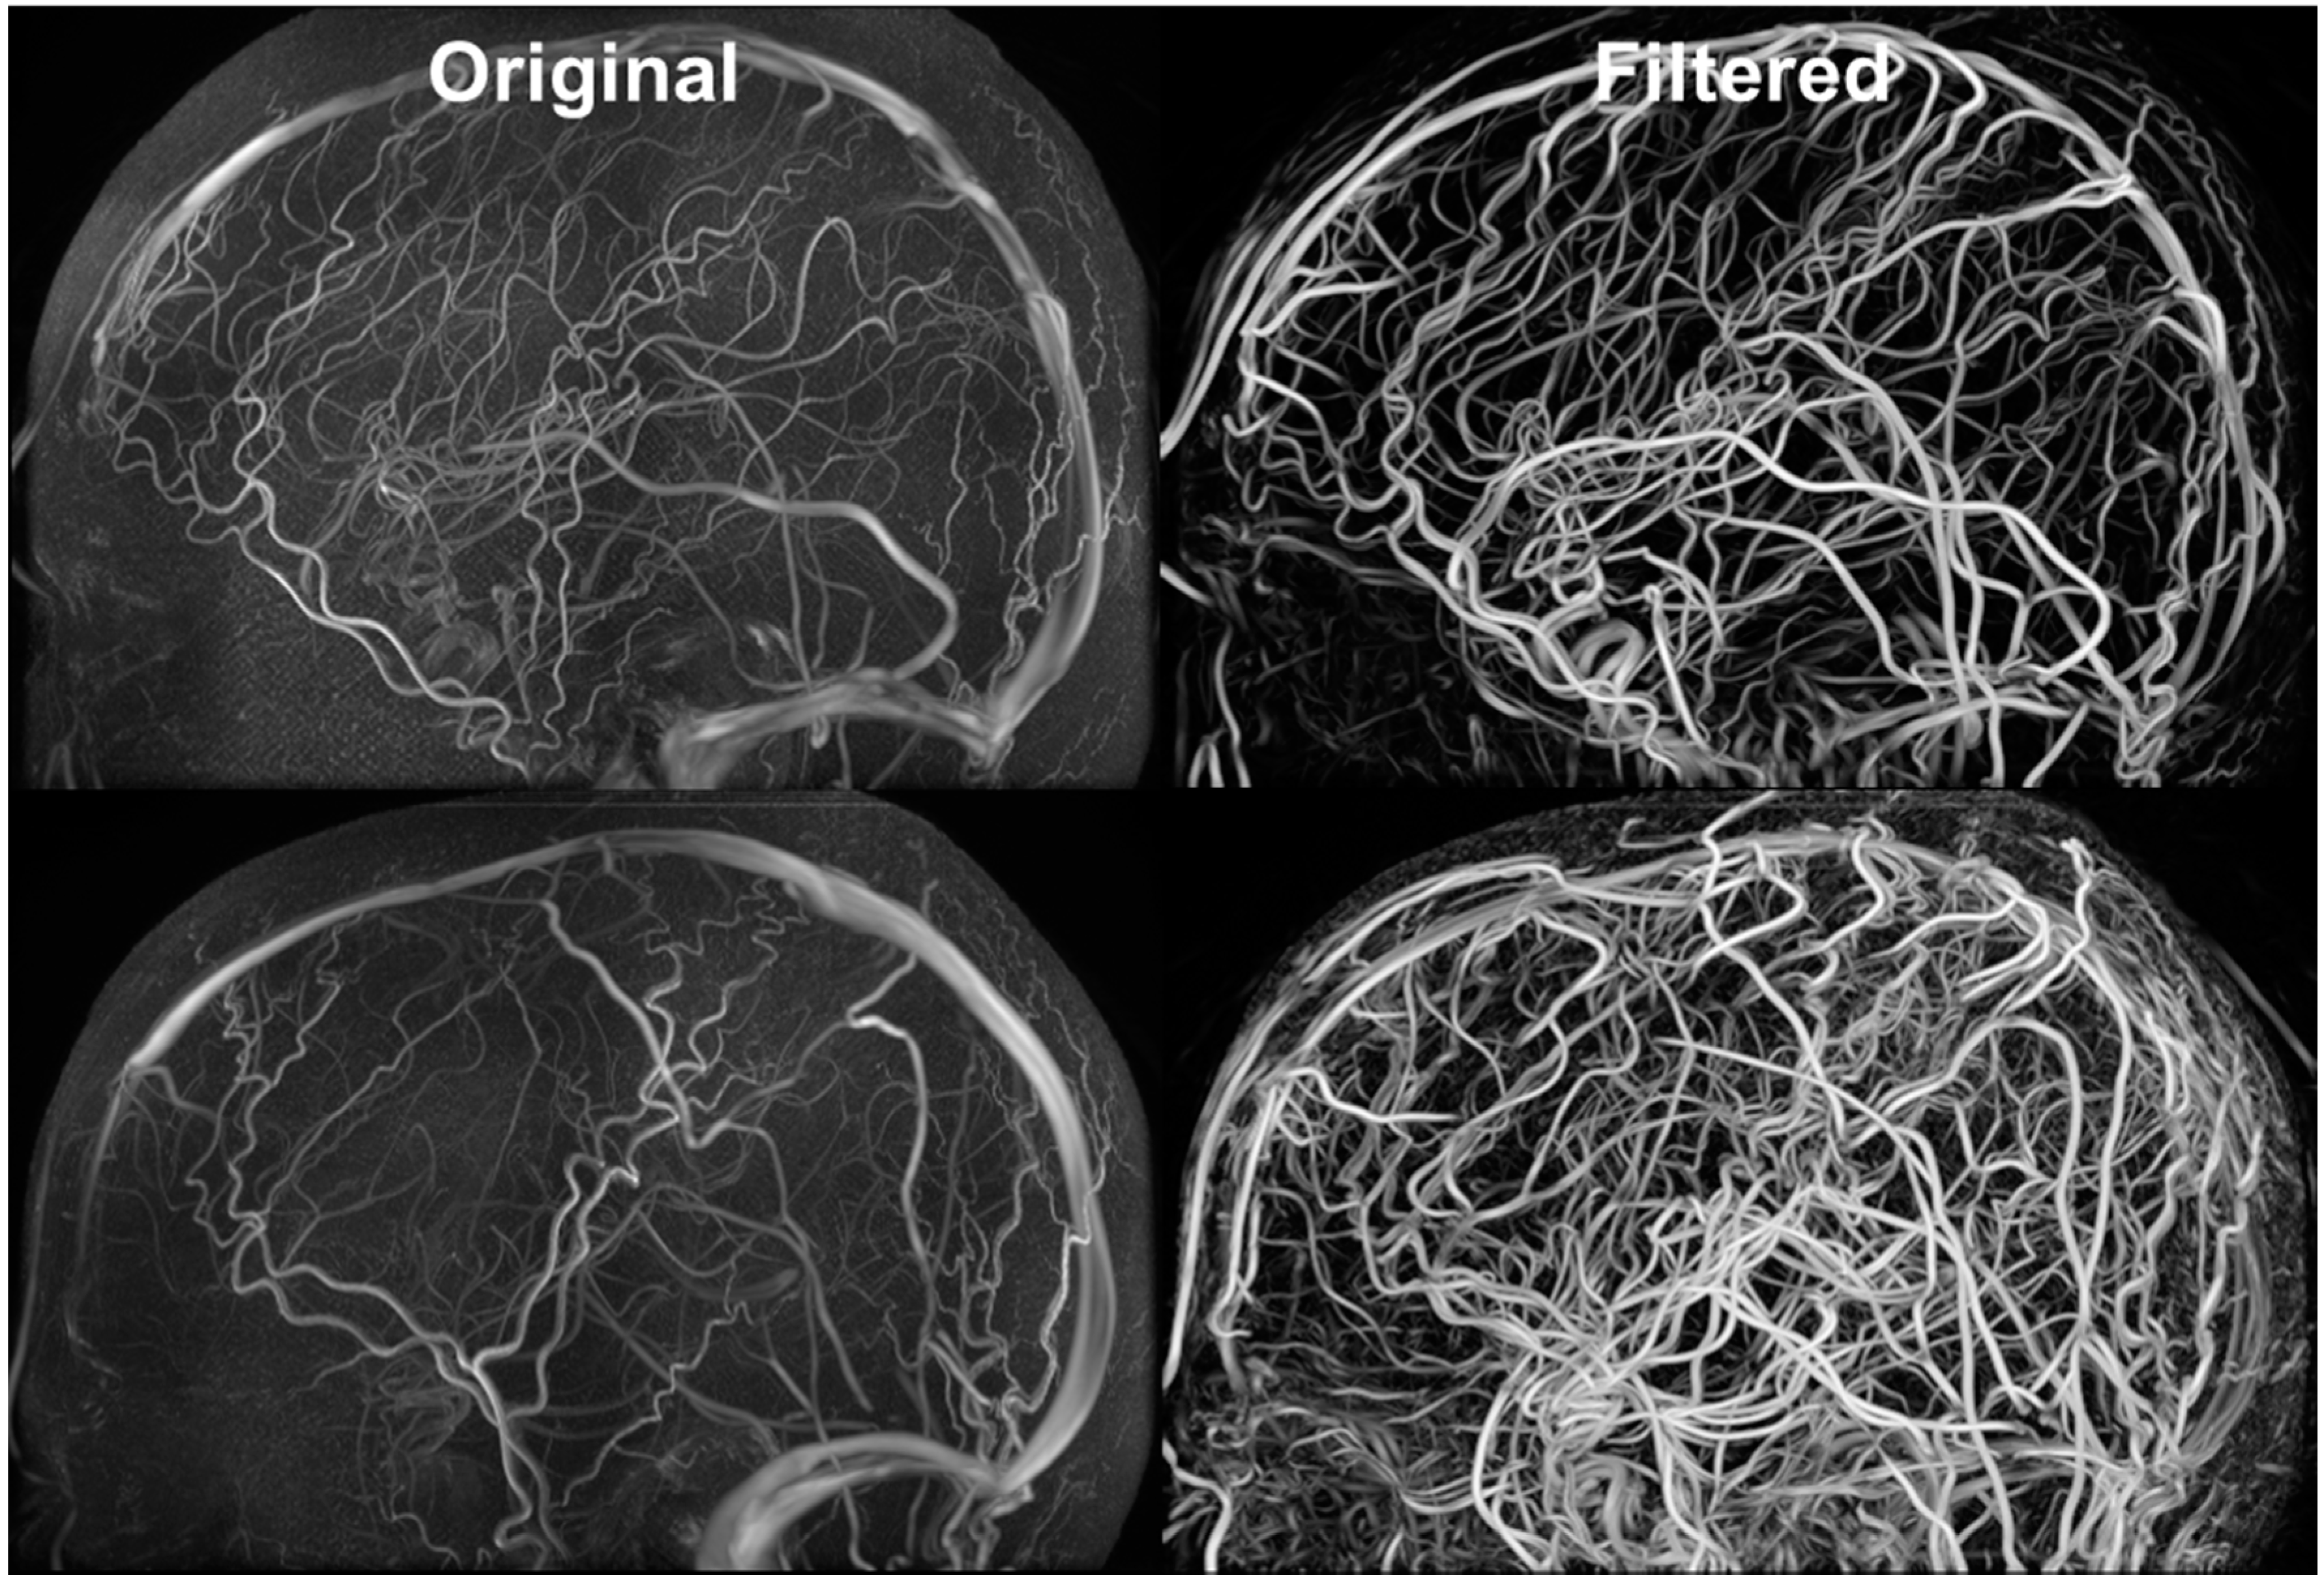

3.4. Vessel Segmentation

Figure 5 exhibits the MRA and MRV along with the filtered images. The MRA has high intensity in the large vessels, but the small vessels have similar intensity to the grey matter. After filtering, all vessels appear brighter which facilitates automatic vessel segmentation. The MRV imaging protocol was designed to remove non-vascular tissues inherently but the small veins are still difficult to detect. After filtering, all veins have high intensity and the filtered image is used for segmentation. The MRA imaging protocol was designed to enhance intensity for high flow areas which also includes signals from the superior sagittal sinus. The contamination from the vein was removed by excluding common voxels between MRA and MRV. After applying our vessel filter, it is shown that the non-vascular tissues were suppressed and small vessels are enhanced. The filter images then served as input for the centerline and diameter extraction. The vessel mesh was reconstructed using the diameter and centerline information shown in Figure 4.

Figure 5.

Filtered MRA for vessel segmentation. Hessian-based filters were implemented for suppressing signals from non-vascular tissues and enhancing vascular tissues. The vessel enhancement allows all vessels to exhibit high intensity values and facilitates automatic vessel segmentation.